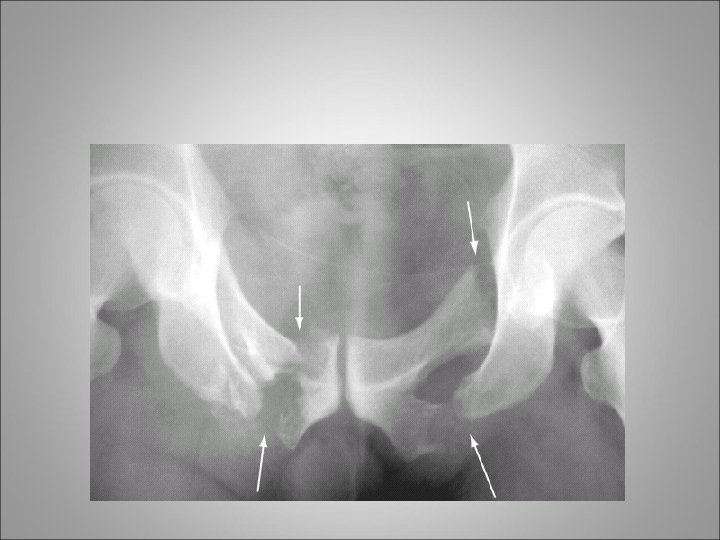

BLADDER INJURIES • The urinary bladder is well protected from external trauma by the bony confines of the pelvis • The majority results from blunt trauma which include motor vehicle accidents, falls and assaults • They are frequently associated with multiple organ trauma, with an average of three coexisting organ injuries and a mortality rate of 20% • Absolute indications for bladder imaging after blunt abdominal trauma are currently limited to two indications: (1) the presence of gross hematuria coexisting with a pelvic fracture and (2) inability to void

BLADDER INJURIES • Traumatic bladder lacerations in children are approximately two times more likely to extend through the bladder neck compared with adults • The diagnosis of a traumatic bladder injury should be assessed by either standard or CT cystography • The amount instilled within the bladder should, at a minimum, be equal to one half of the estimated bladder capacity for age • All patients with traumatic bladder lacerations, either extraperitoneal or intraperitoneal, should initially be treated with intravenous antibiotics with oral antibiotic therapy continued for 48 hours after removal of bladder catheters

Intra and extra peritoneal bladder rupture

BLADDER INJURIES • In extraperitoneal bladder injury, consideration for open surgical intervention should be given if a bony spicule is found to protrude into the bladder on CT evaluation or if concern for a bladder neck laceration is present • If these two complications are not present, management by an indwelling urethral catheter can be considered • Urinary drainage via the bladder catheter is maintained for 7 to 10 days, and a cystogram should be obtained to verify healing of the injury before catheter removal • In intraperitoneal bladder injuries, open surgical repair of the laceration is the recommended treatment modality